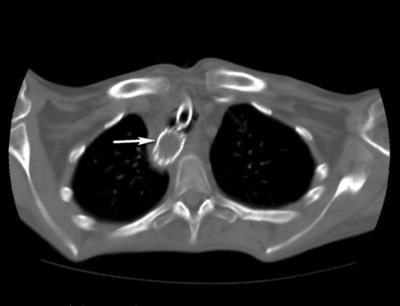

IV stádiumban nyelőcsőrák felvett betegek sürgősségi SRI utáni 7. napon endoszkópos bougienage és SP klinikai-instrumentális mediastinitis állítható képet (ábra. 1).

Kezelés Intézet Sürgősségi ellátás végrehajtása három szakaszból áll. Először is, hogy biztosítsa a megfelelő enterális táplálás készült Laparotomiát Nissen LF, gastrostomia Kader. Miután javítása tápláltsági állapota, köpölyözés aspirációs tüdőgyulladás második szakaszban végzett jobb thoracotomia, reszekció mellkasi nyelőcső, egy bal oldali kolotomiyu, megszüntetése tracheo fistula a műanyag légcső defektus izom- periosteum lebeny, traheofissuru képződik a T-alakú cső. Működés közben a stent távolítani. Miután 8 hónappal a beteg kialakított mesterséges nyelőcső a vastagbél annak retrosternalis helyét.